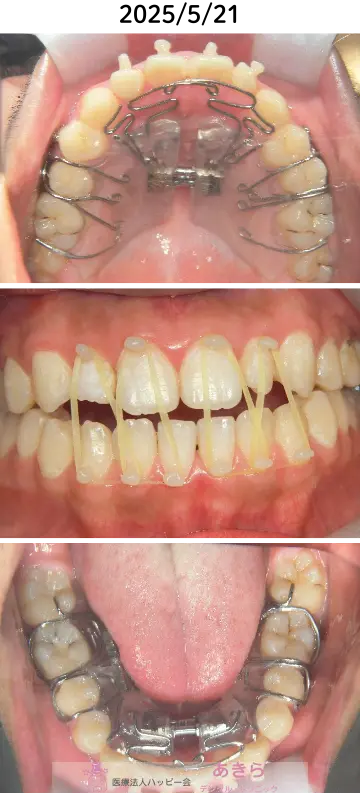

2025年5月21日 口腔内写真(顎間ゴムにて前歯部牽引)

- 2025年5月 前歯部の開咬の改善を希望のため『顎間ゴム併用』牽引開始

- 8月保定(牽引終了)